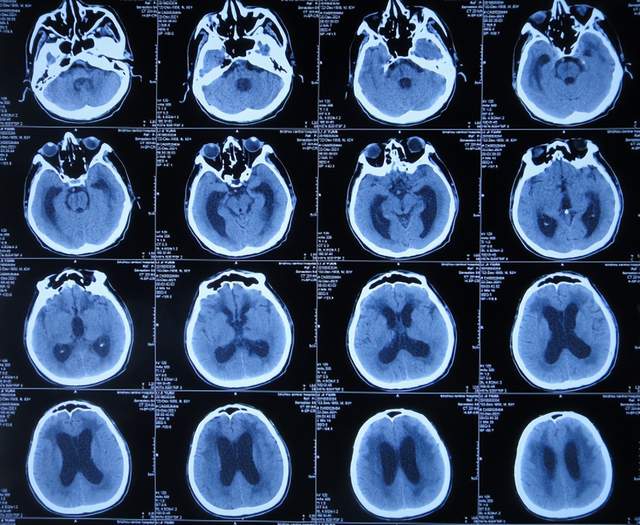

腰大池引流术后4天即2021年9月12日,查头颅CT示脑室内积血基本消失(图-5)。

图-5:2021年9月12日头颅CT

拔除腰大池引流管后3天即2021年9月23日,查头颅CT示(图-6)后继续给予保守治疗。

图-6:2021年9月23日头颅CT

腰大池引流管拔除后13天即2021年10月3日,患者恢复至可以搀扶下行走约20米,能简单言语,查头颅CT较2021年9月23日认为没有明显变化(图-7)。

图-7:2021年10月3日头颅CT

但继续保留治疗20余天的时间内,患者逐渐出现意识变差,走路变差,至2021年11月3日(腰大池引流管拔除后31天),病情变重致不能走路,不能言语,查头颅CT(图-8)后考虑脑积水,给予腰椎穿刺治疗。

图-8:2021年11月3日头颅CT

但腰椎穿刺治疗7天病情无明显改善,于2021年11月10日(住院治疗2月余)出院回家休养,出院时头颅CT示仍有脑积水(图-9);出院时:意识差,不能走路,不能言语。

图-9:2021年11月10日头颅CT